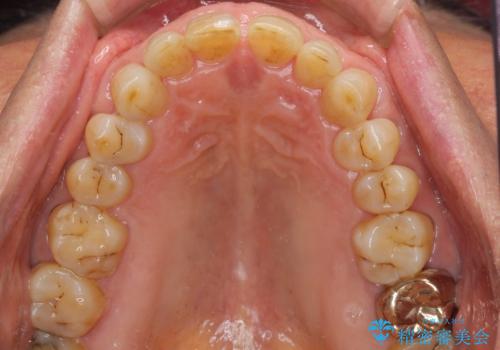

- 前歯のすきっ歯を気にして来院された患者様です。

矯正かオールセラミックか、治療の選択がありましたが、ご年齢や色の濃い点を考慮してオールセラミッククラウンにて補綴することとしました。

折角なのできれいに仕上げたいとのことで、オーダーメイドタイプのクラウンを選択されました。色調を周りのご自身の歯と合わせることができるため、自然な仕上がりをご希望の方におすすめです。